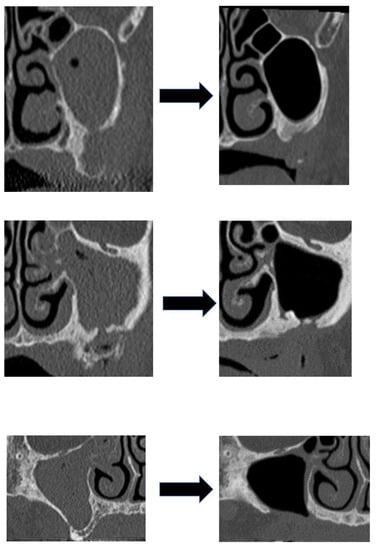

| None | 7 | 6 | 1 | 7 | 21 |

| Intraoperative irrigation | 0 | 3 | 0 | 10 | 13 |

| Total | 7 | 9 | 1 | 17 | 34 |